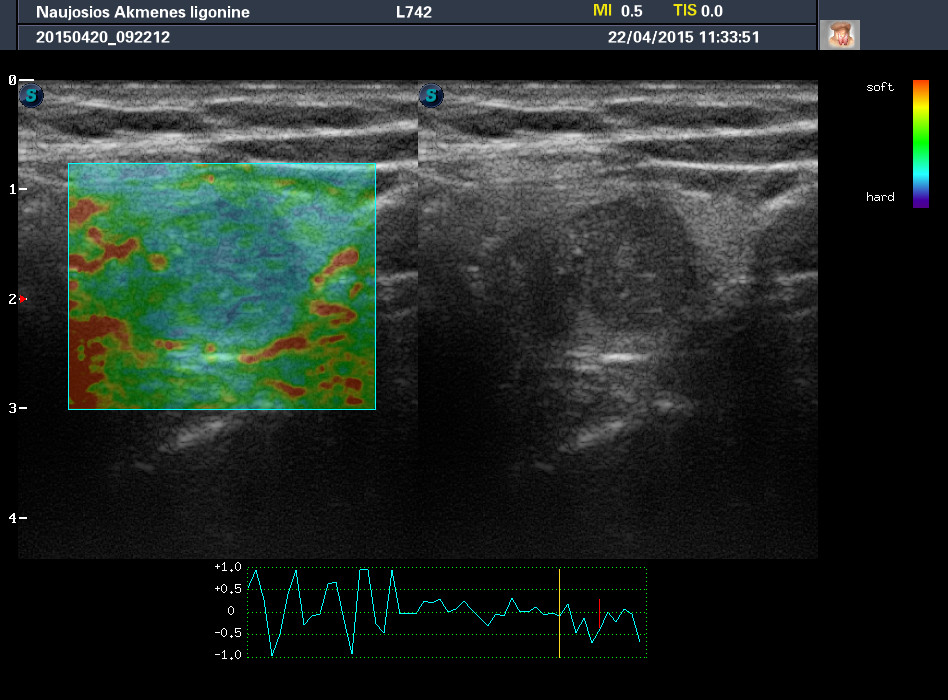

Случай 2

Женщина 61 год, жалоб нет. Рост узла за год +1 мм. Регионарные ЛУ не увеличены.

apr222015113351_29.jpg

1-й узел злокачественный, а 2-й ,скорее всего, доброкачественный. Но,понятное дело, нужна пункция и было бы здорово узнать результат.

Mattiola писал(а): И,простите, что за исследование на сканах, не на видео? Я такого не делаю и,к сожалению, не знаю,как интерпретировать его(

Эластография. http://www.medison.ru/si/art380.htm